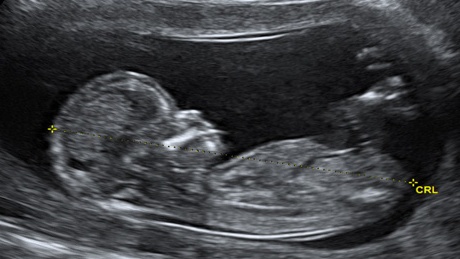

Siêu âm là một công cụ có giá trị và không xâm lấn, có thể được sử dụng để đánh giá nguy cơ và khả năng trẻ mắc hội chứng Down.

Siêu âm là một phương pháp sàng lọc, có thể được thực hiện trong tam cá nguyệt thứ nhất và thứ hai. Các đặc điểm trên hình ảnh siêu âm có thể chỉ ra hội chứng Down bao gồm: